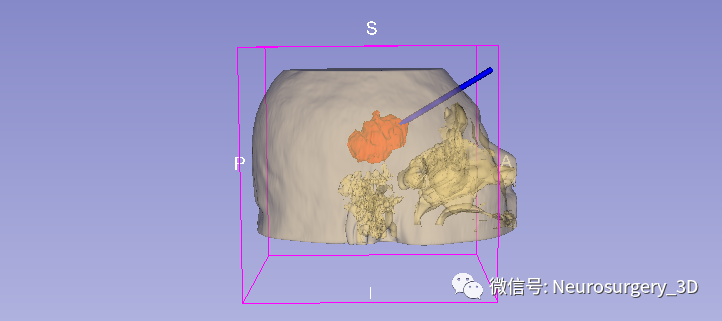

2、可透视化显示颅内血肿形态

1、利用Ruler测量出穿刺血肿靶点至穿刺外口的距离,并设计出穿刺路径顺血肿长轴走形在血肿中心(并非如下图所示所有穿刺路径均与矢状面平行、请注意穿刺深度),避开颅内重要结构如额窦、上矢状窦等。

入颅点避开了额窦、上矢状窦

透视化血肿状态下显示穿刺路径走形在血肿中心